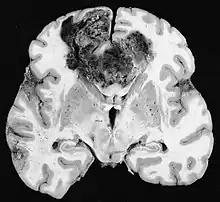

Les tumeurs des cellules gliales les plus courantes et les plus malignes sont les glioblastomes. Ils consistent en une masse hétérogène de cellules d'astrocytome peu différenciées principalement chez l'adulte. Ils surviennent généralement dans les hémisphères cérébraux, plus rarement dans le tronc cérébral ou la moelle épinière. Sauf dans de très rares cas, comme toutes les tumeurs cérébrales, elles ne s'étendent pas au-delà des structures du système nerveux central.

Le glioblastome peut provenir d'une forme diffuse (II. grade) ou un astrocytome anaplasique (III. grade) développer. Dans ce dernier cas, il est dit secondaire. Cependant, lorsqu'elle survient sans antécédent ni signe de malignité antérieure, on parle de maladie primaire. Les glioblastomes sont traités par chirurgie, radiothérapie et chimiothérapie. Ils sont difficiles à guérir et rares sont les cas qui survivent au-delà de trois ans.

Les métastases cérébrales sont les néoplasmes intracrâniens les plus courants chez les adultes, étant dix fois plus fréquents que les tumeurs cérébrales primaires. Ils marchent à 20 jusqu'à 40 pour cent des adultes atteints de cancer et sont principalement associés au cancer du poumon et du sein et au mélanome . Ces lésions résultent de la propagation des cellules cancéreuses dans la circulation sanguine et surviennent le plus souvent à la jonction de la matière grise et blanche, où la section transversale des vaisseaux sanguins change, emprisonnant les embolies de cellules tumorales . 80 % des lésions surviennent dans les hémisphères cérébraux, 15 pour cent dans le cervelet et 5 pour cent dans le tronc cérébral. Environ 80 % des patients ont des antécédents de cancer systémique et 70 pour cent ont de multiples métastases cérébrales.